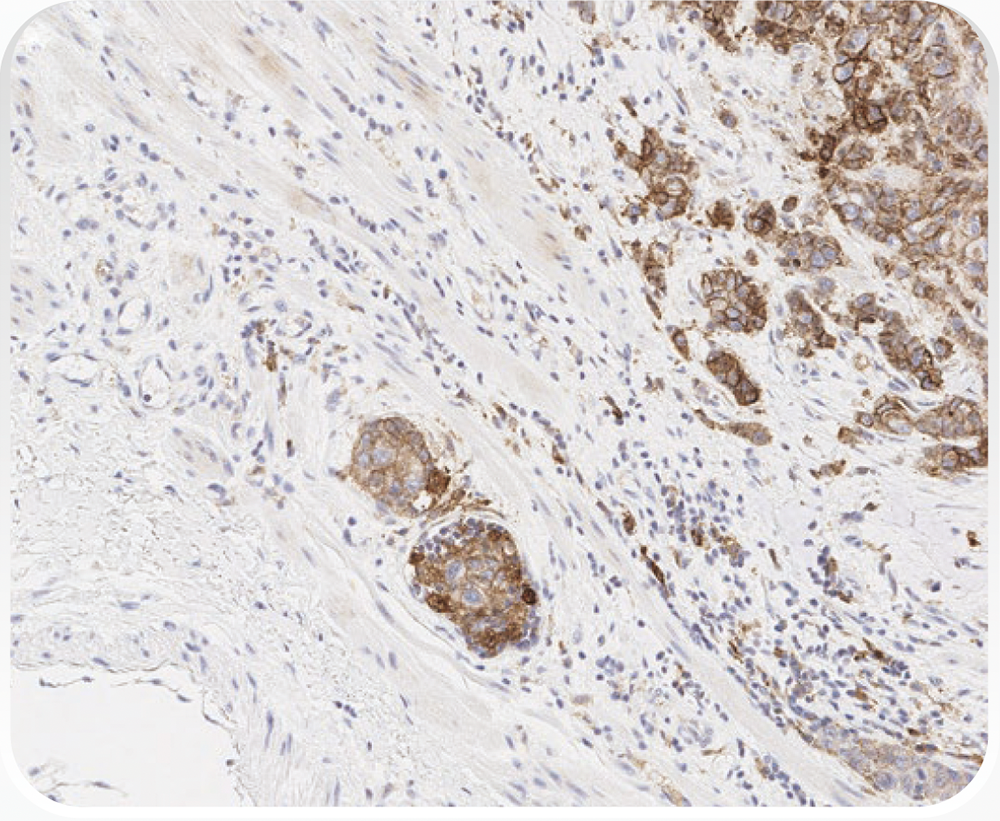

PD-L1の発現状況の指標であるCPSは、PD-L1を発現しているがん細胞及びリンパ球やマクロファージといった免疫細胞をカウントし、その数をがん細胞の総数で除し100を乗じることで算出されます。CPSはTPSと異なり、浸潤癌巣で判定します。

CPSの算出には、以下に示す計算式を用います。

CPSはTPSと異なり、浸潤癌巣で判定します。

CPSの評価において、計算式の分子あるいは分母に組み入れる細胞あるいは除外する細胞の種類は以下の表に示す通りです。また、各種細胞におけるPD-L1の染色像については、こちらをご参照ください。

*1 MICでは、細胞質に対する細胞核の比率が高いため、多くの場合細胞膜染色と細胞質染色とは判別不能です。

このため、MICの細胞膜染色または細胞質染色はCPSの分子に含めます。

*2 隣接するMICは腫瘍と同じ20倍視野内にあると定義されます。しかし、腫瘍に対する反応に直接関連しないMICは除外されます。

*3 マクロファージと組織球は同じ細胞と考えられます。